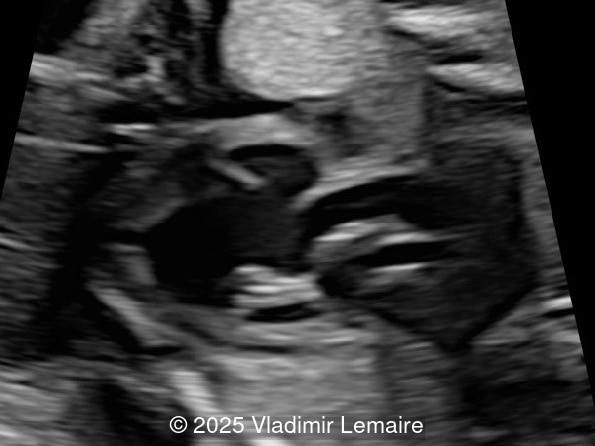

We present a case of isolated tricuspid atresia type 1 with persistent left superior vena cava. No other extracardiac anomalies were found. Our diagnosis was confirmed after birth.

In the images below, the abbreviations are as follows: RA: right atrium; RV: right ventricle; LV: left ventricle; MV: mitral valve; LA: left atrium; FO: foramen ovale; SVC: superior vena cava; LSVC: left superior vena cava; PV: pulmonary veins; PA: pulmonary artery; MPA: main pulmonary artery; RPA: right pulmonary artery; AO: aorta; dAO: descending aorta; aAO: ascending aorta; DA: ductus arteriosus; T: trachea; * marks the ventricular septal defect.

Tricuspid atresia is a rare anomaly, with an incidence of 0.08 per 1,000 live births, and is characterized by the lack of communication between the right atrium and ventricle. As a result, the right ventricle is hypoplastic. The tricuspid valve apparatus does not develop in the majority of cases, and the right atrioventricular junction appears as echogenic thickened tissue on ultrasound examination. An inlet type ventricular septal defect is always present, and the size of the right ventricle depends on the size of the ventricular septal defect. As a consequence of the obstructed tricuspid valve, a large interatrial communication, in the form of a widely patent foramen ovale or atrial septal defect, is necessary.

The four-chamber view in tricuspid atresia is diagnostic. It reveals a small right ventricle, a ventricular septal defect, and the absence of a right-sided atrioventricular junction. The size of the right ventricle mainly depends on the size of the ventricular septal defect: the smaller the ventricular septal defect, the smaller the right ventricle. Its contractility is normal with no myocardial thickening. The atretic tricuspid valve appears as echogenic thickened tissue and the right atrium is slightly dilated. The interatrial communication is large and there is often a redundant flap of the septum secundum that bulges into the left atrium. The interatrial and interventricular septa are malaligned.